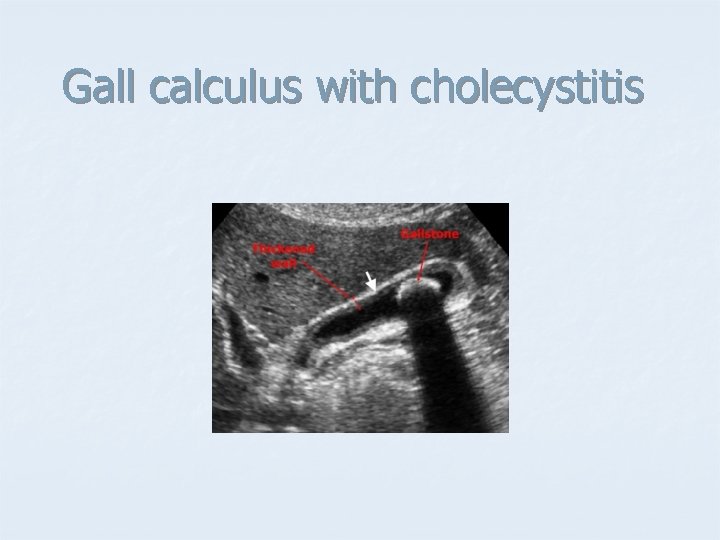

Gall calculus with cholecystitis